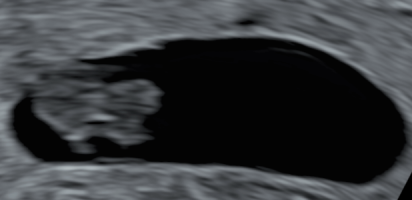

Fikk du høre hjertet når du var så kort på vei? Jeg fikk beskjed at de ikke ønsket å bruke doppler fordi det kunne forstyrre de når de var så små. Fikk bare sett hjertet slå. Jeg var 8+5.Vi hadde privat ultralyd 7+0 (mensdato 7+4), hvor vi hørte hjerteslag, så plommesekken, og lille ble målt til 8 mm og 7+5 (unøyaktig så tidlig sa hun)Vis vedlegget 474796Vis vedlegget 474797